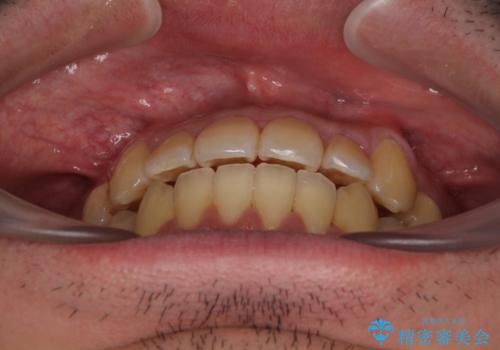

デコボコが解消されると歯列が拡大される方向に動くため、出っ歯のような仕上がりとなることがあります。舌の突出癖を改善するトレーニングをしっかりと行っていただくことで、突出を抑制することができます。